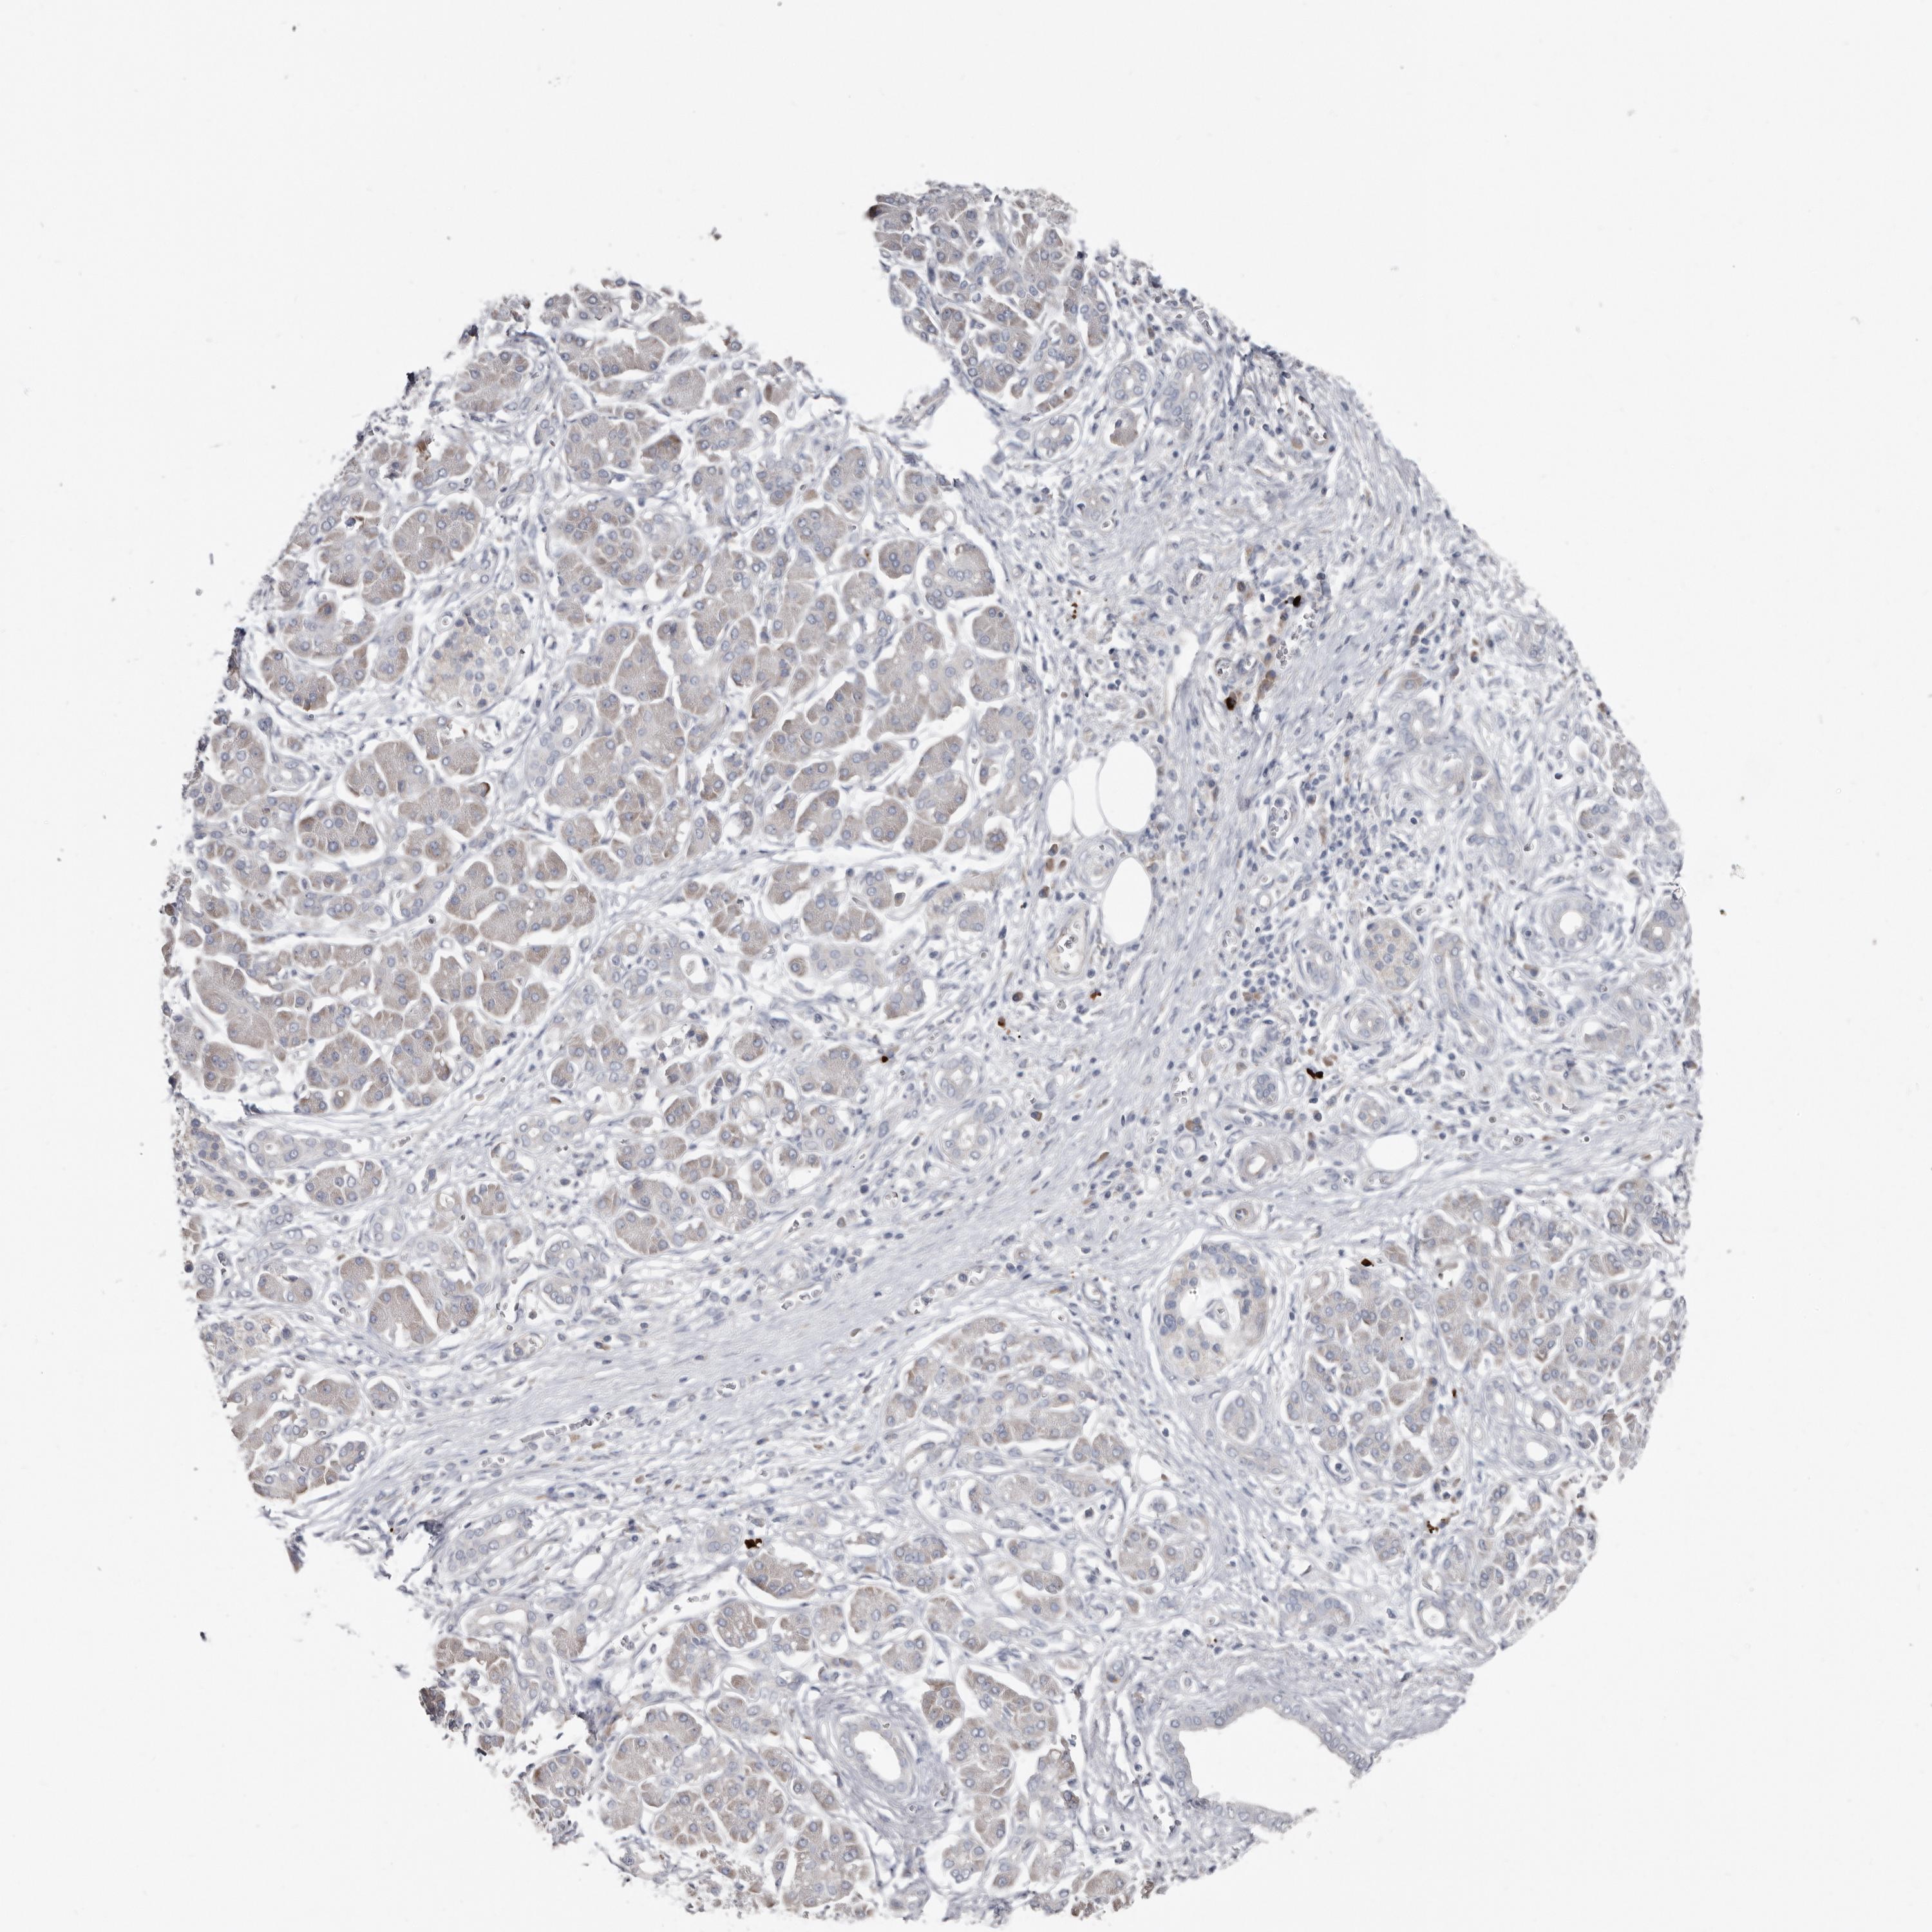

PANCREATIC CANCER - Protein expressioni

A mouse-over function shows sample information and annotation data. Click on an image to view it in a full screen mode. Samples can be filtered based on level of antibody staining by selecting one or several of the following categories: high, medium, low and not detected. The assay and annotation is described here.

Note that samples used for immunohistochemistry by the Human Protein Atlas do not correspond to samples in the TCGA dataset.

Antibody stainingi

Antibody staining in the annotated cell types in the current human tissue is reported as not detected, low, medium, or high, based on conventional immunohistochemistry profiling in selected tissues. This score is based on the combination of the staining intensity and fraction of stained cells.

Each image is clickable and will lead to virtual microscopy that enables deeper exploration of all samples and also displays staining intensity scores, fraction scores and subcellular localization as well as patient and tissue information for each sample.

Antibody HPA025019

Antibody HPA029553

Adenocarcinoma, NOS